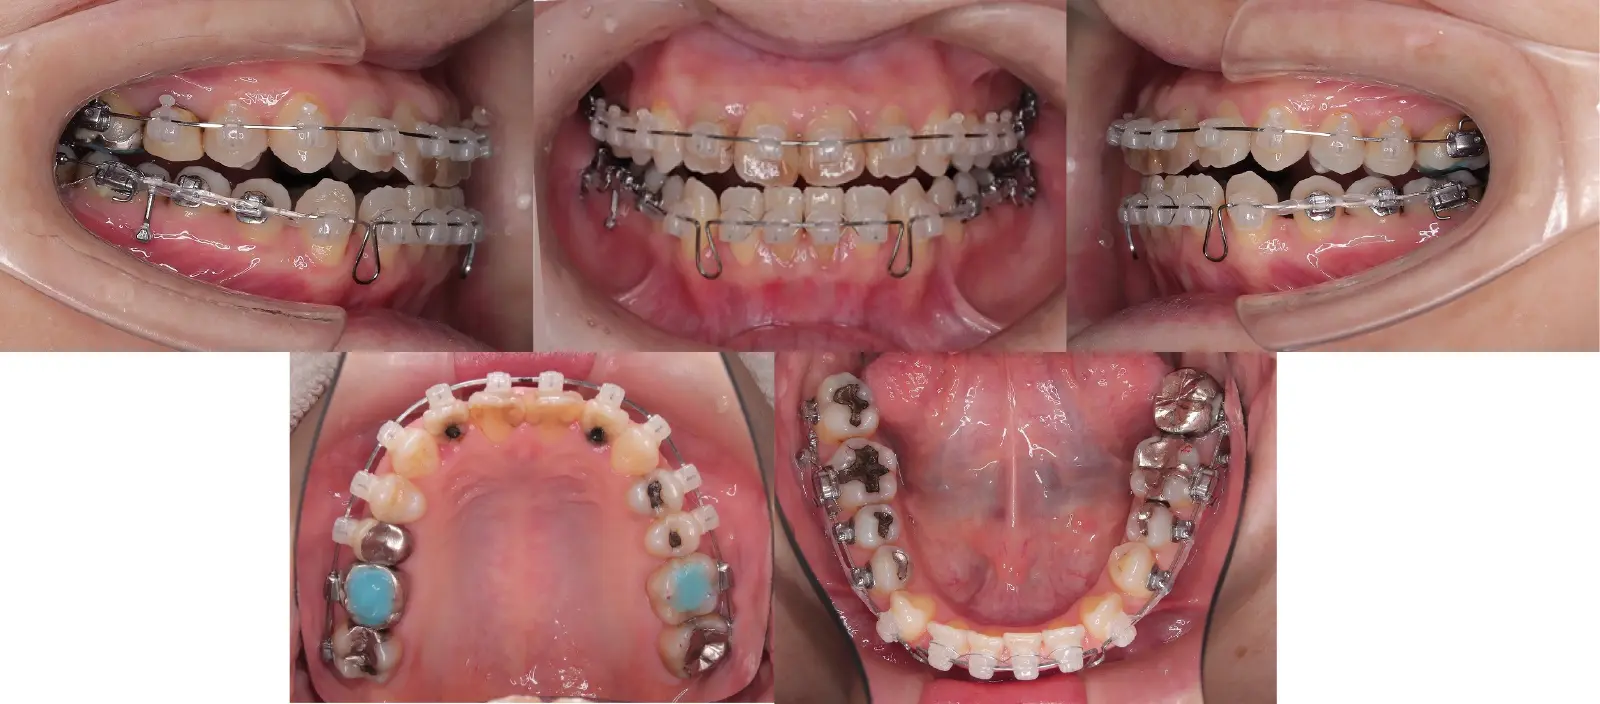

叢生を伴う骨格性反対咬合

- 主訴

受け口と歯がガタガタ

- 年齢

10代

- 治療期間

3年3ヶ月

- 治療回数

30回

- 治療に用いた主な装置

カスタマイズタイプリンガル矯正装置(インコグニート)

- 治療費

1,350,000円(税別)トータル料金

- 抜歯部位

上顎右側第一小臼歯、上顎左側第2小臼歯、下顎両側第一小臼歯